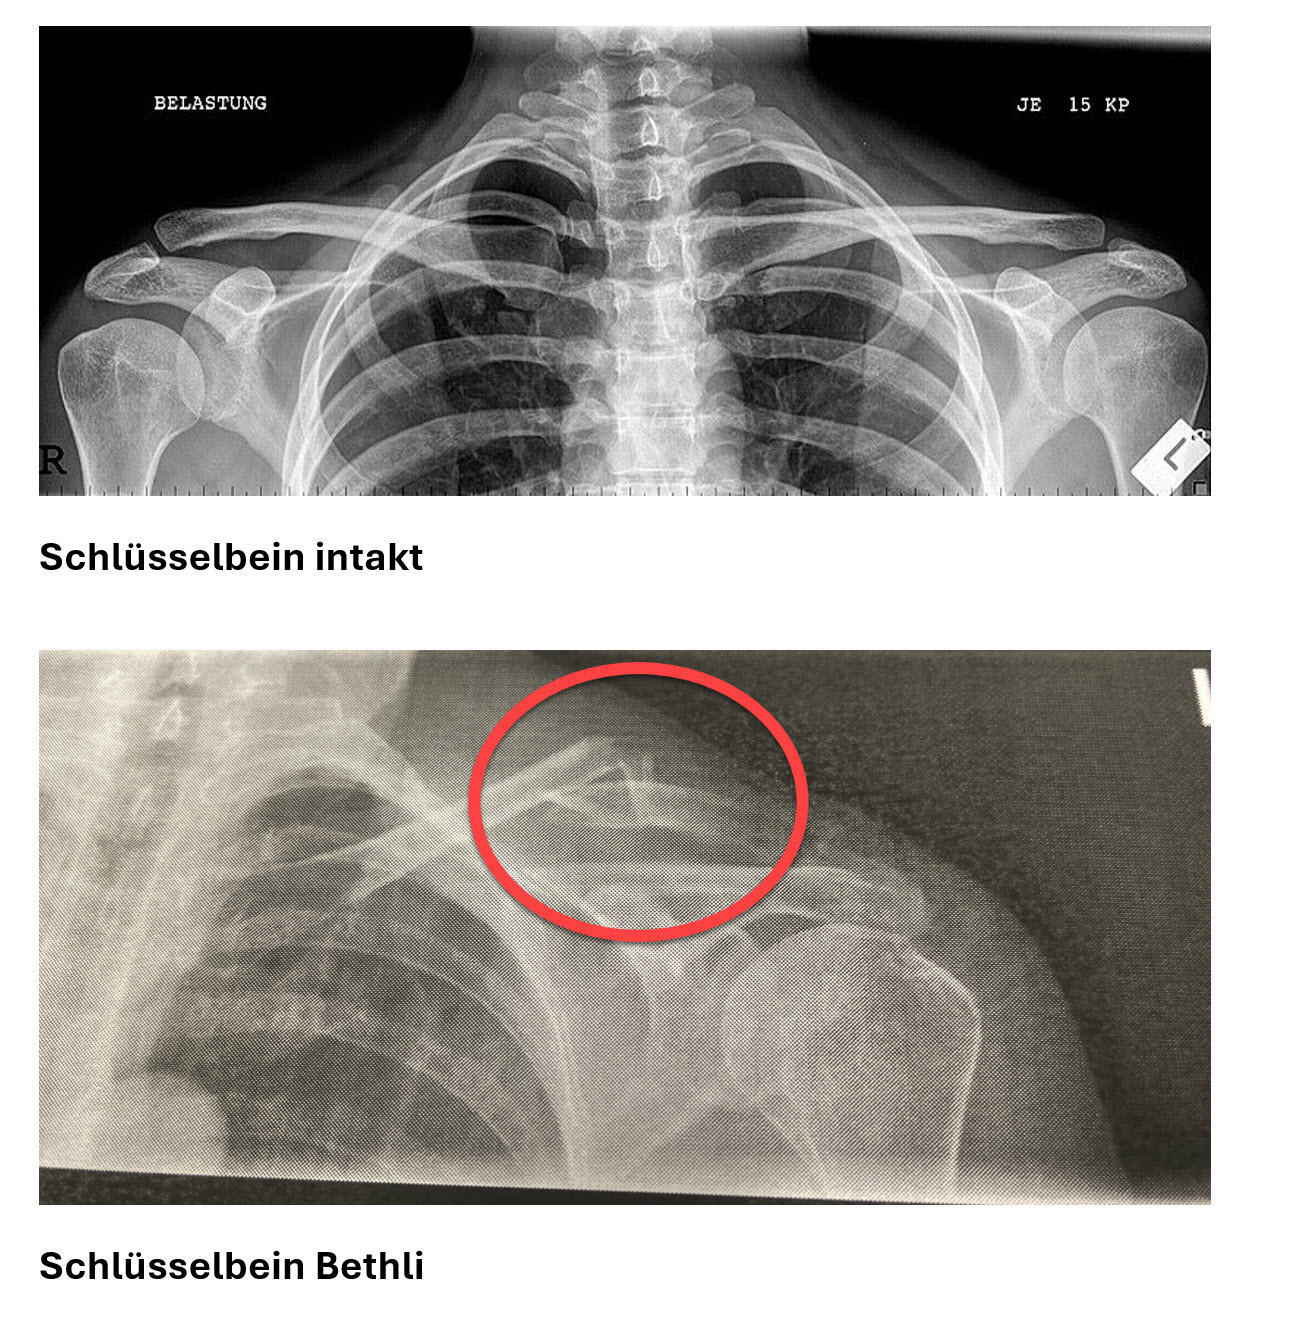

Dieses Jahr haben wir Weihnachten in „kleinerem Rahmen“ gefeiert. Sonja und Fabio sowie Tamina und Yannick sind bei ihren Eltern in Lette bzw. Hägglingen. Und Bethli liegt mit einem gebrochenen Schlüsselbein im Spital Muri. Sie wurde von allen vermisst. Immerhin hat sie bzw. das corpus delicti es auf eine Aufnahme geschafft.